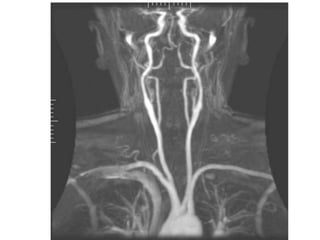

Initial screening test is noninvasive , either DS or MRA.

TOF MRA is less sensitive DS (75%Vs 87%) but more specific (88%Vs

46%).

Concordance in TOF and DS is more sensitive(96%) and specific

(85%) than either test alone.(Johnston, and Goldstein et al 2001)

2D TOF MRA over estimates the degree of stenosis.

3D TOF MRA is less likely to overestimate stenosis.

Combination of 2D and 3D TOF MRA results in greater specificity.

 ‘FLOW GAP’- segmental dropout , When the stenosis is more than

70%. ( Heiserman JE et al 1996)

3D CEMRA have greater anatomical coverage in terms of surface

morphology, carotid bifurcation, near occlusion

3D CE MRA is more sensitive(94.6% vs 91.2%) and specific ( 88.3%vs

91.9%) than TOF MRA for high grade ICA stenosis.

Carotid atherosclerotic narrowing